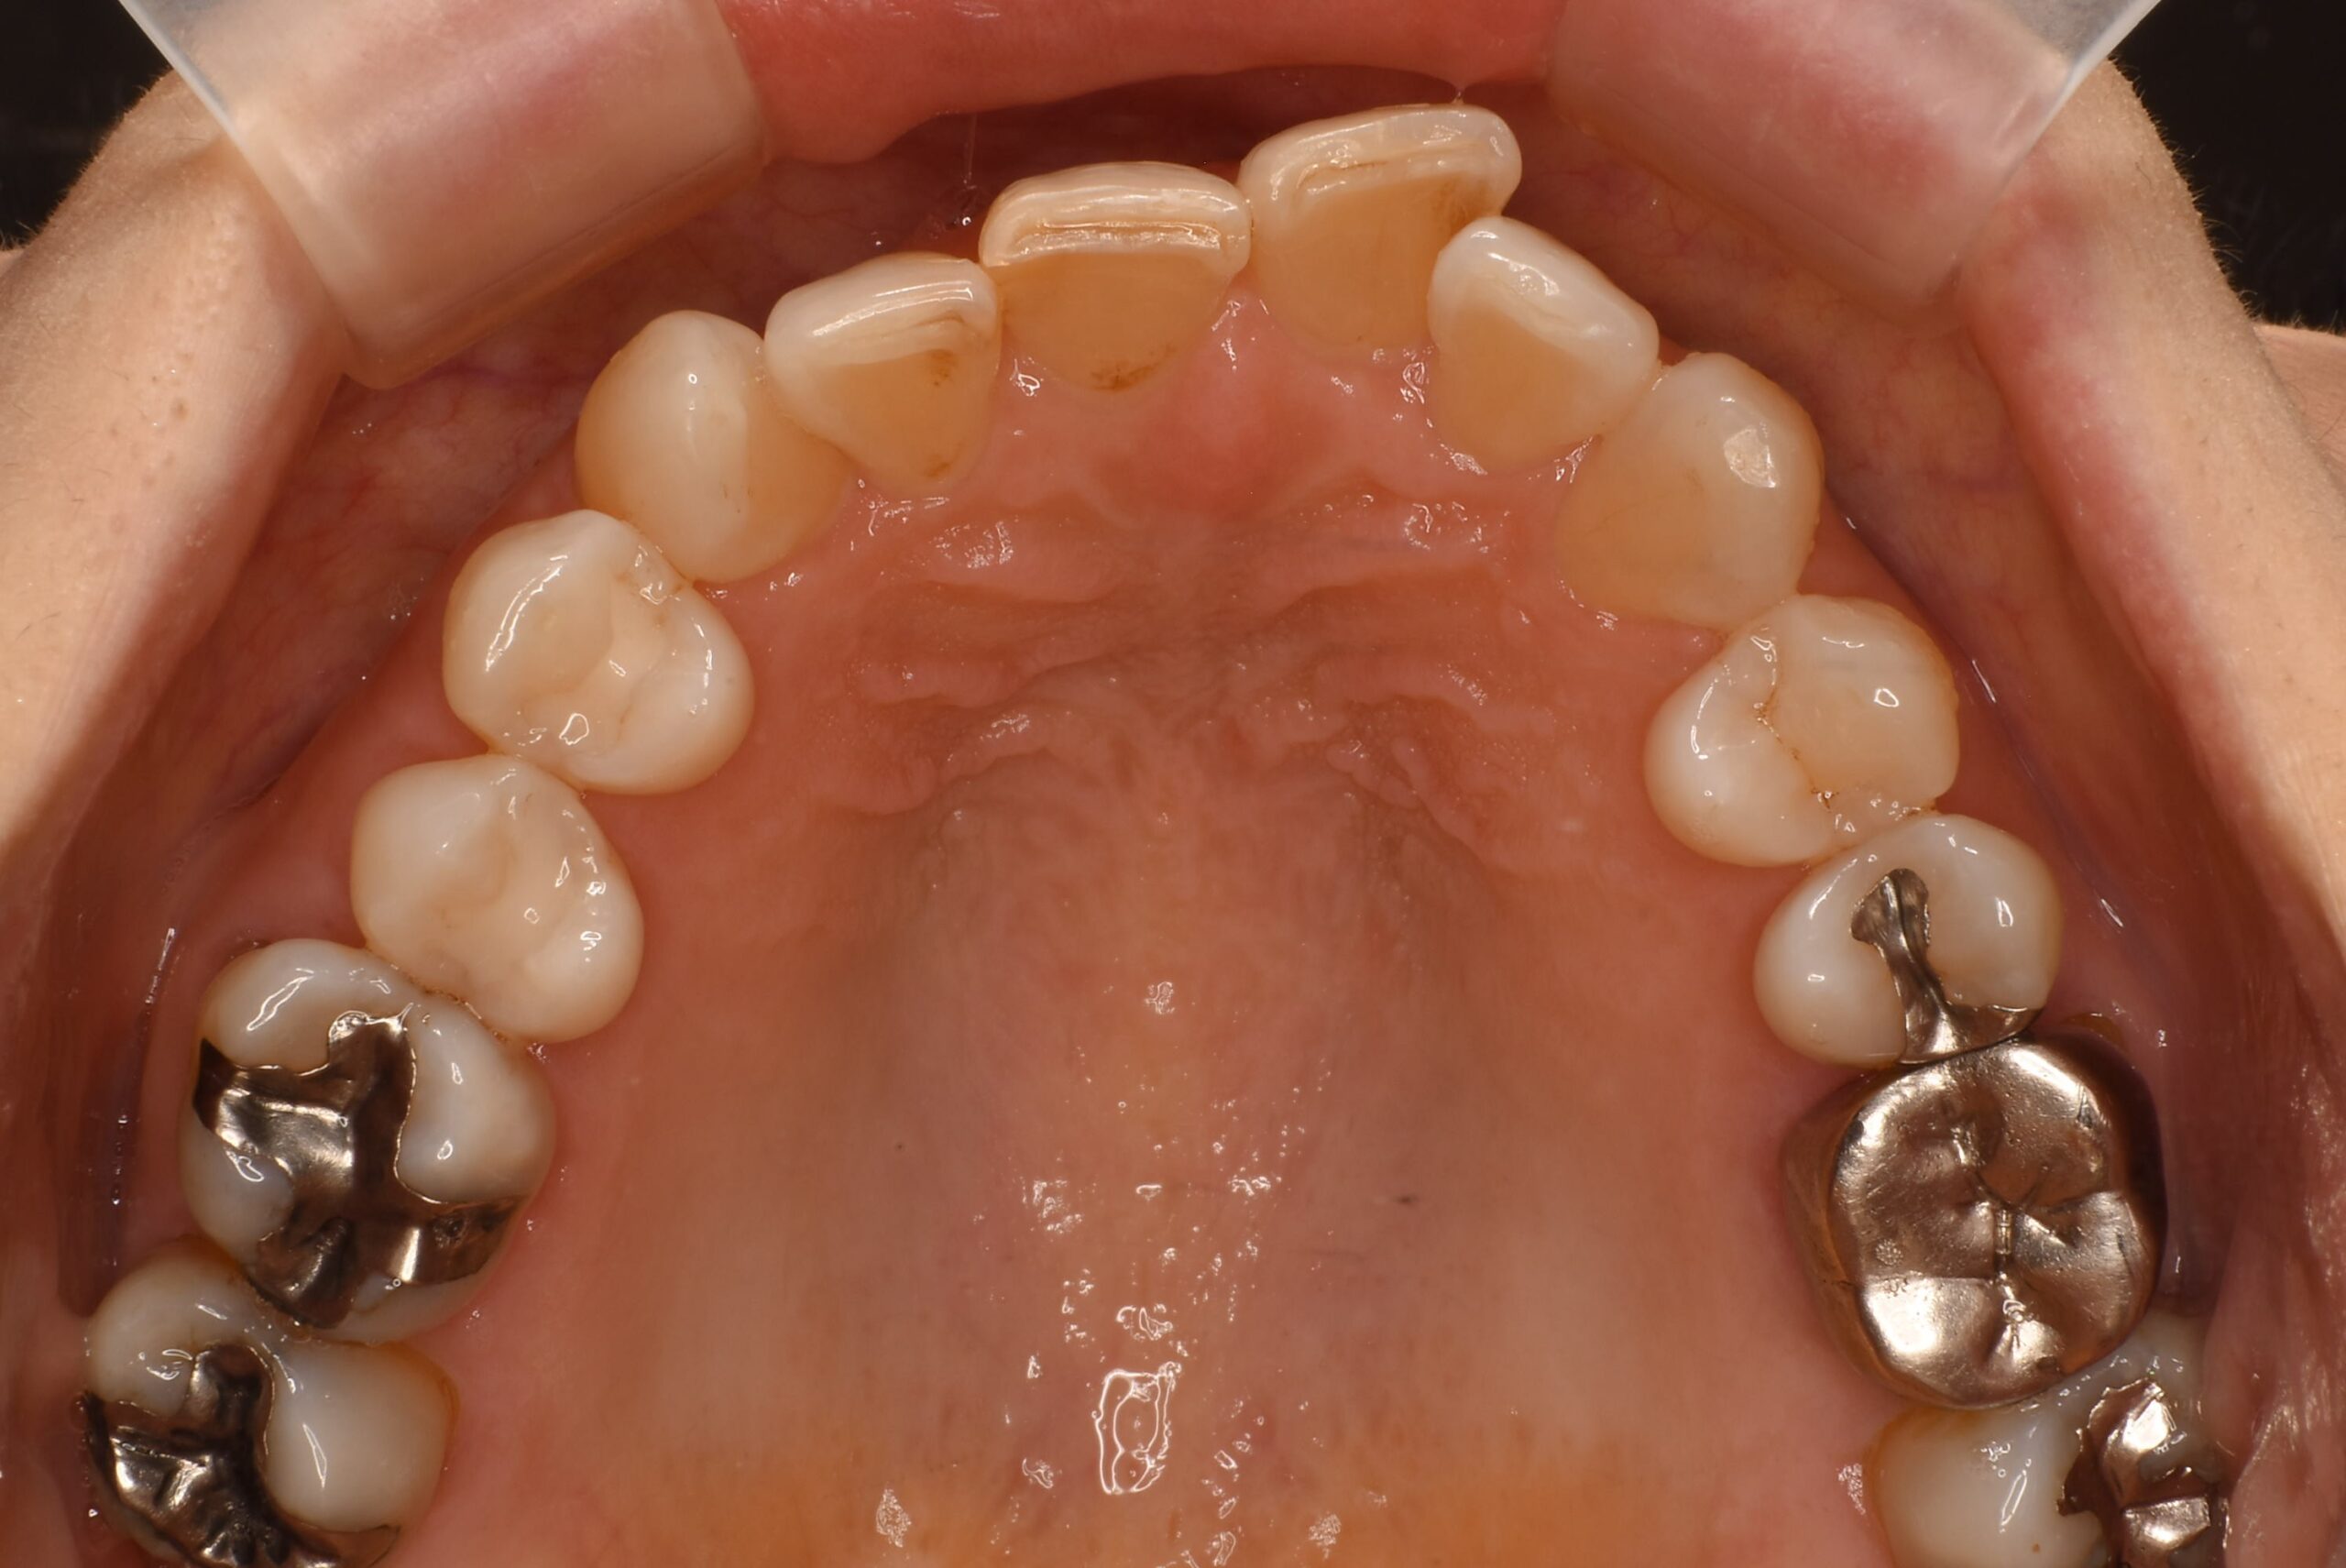

治療前上咬合面